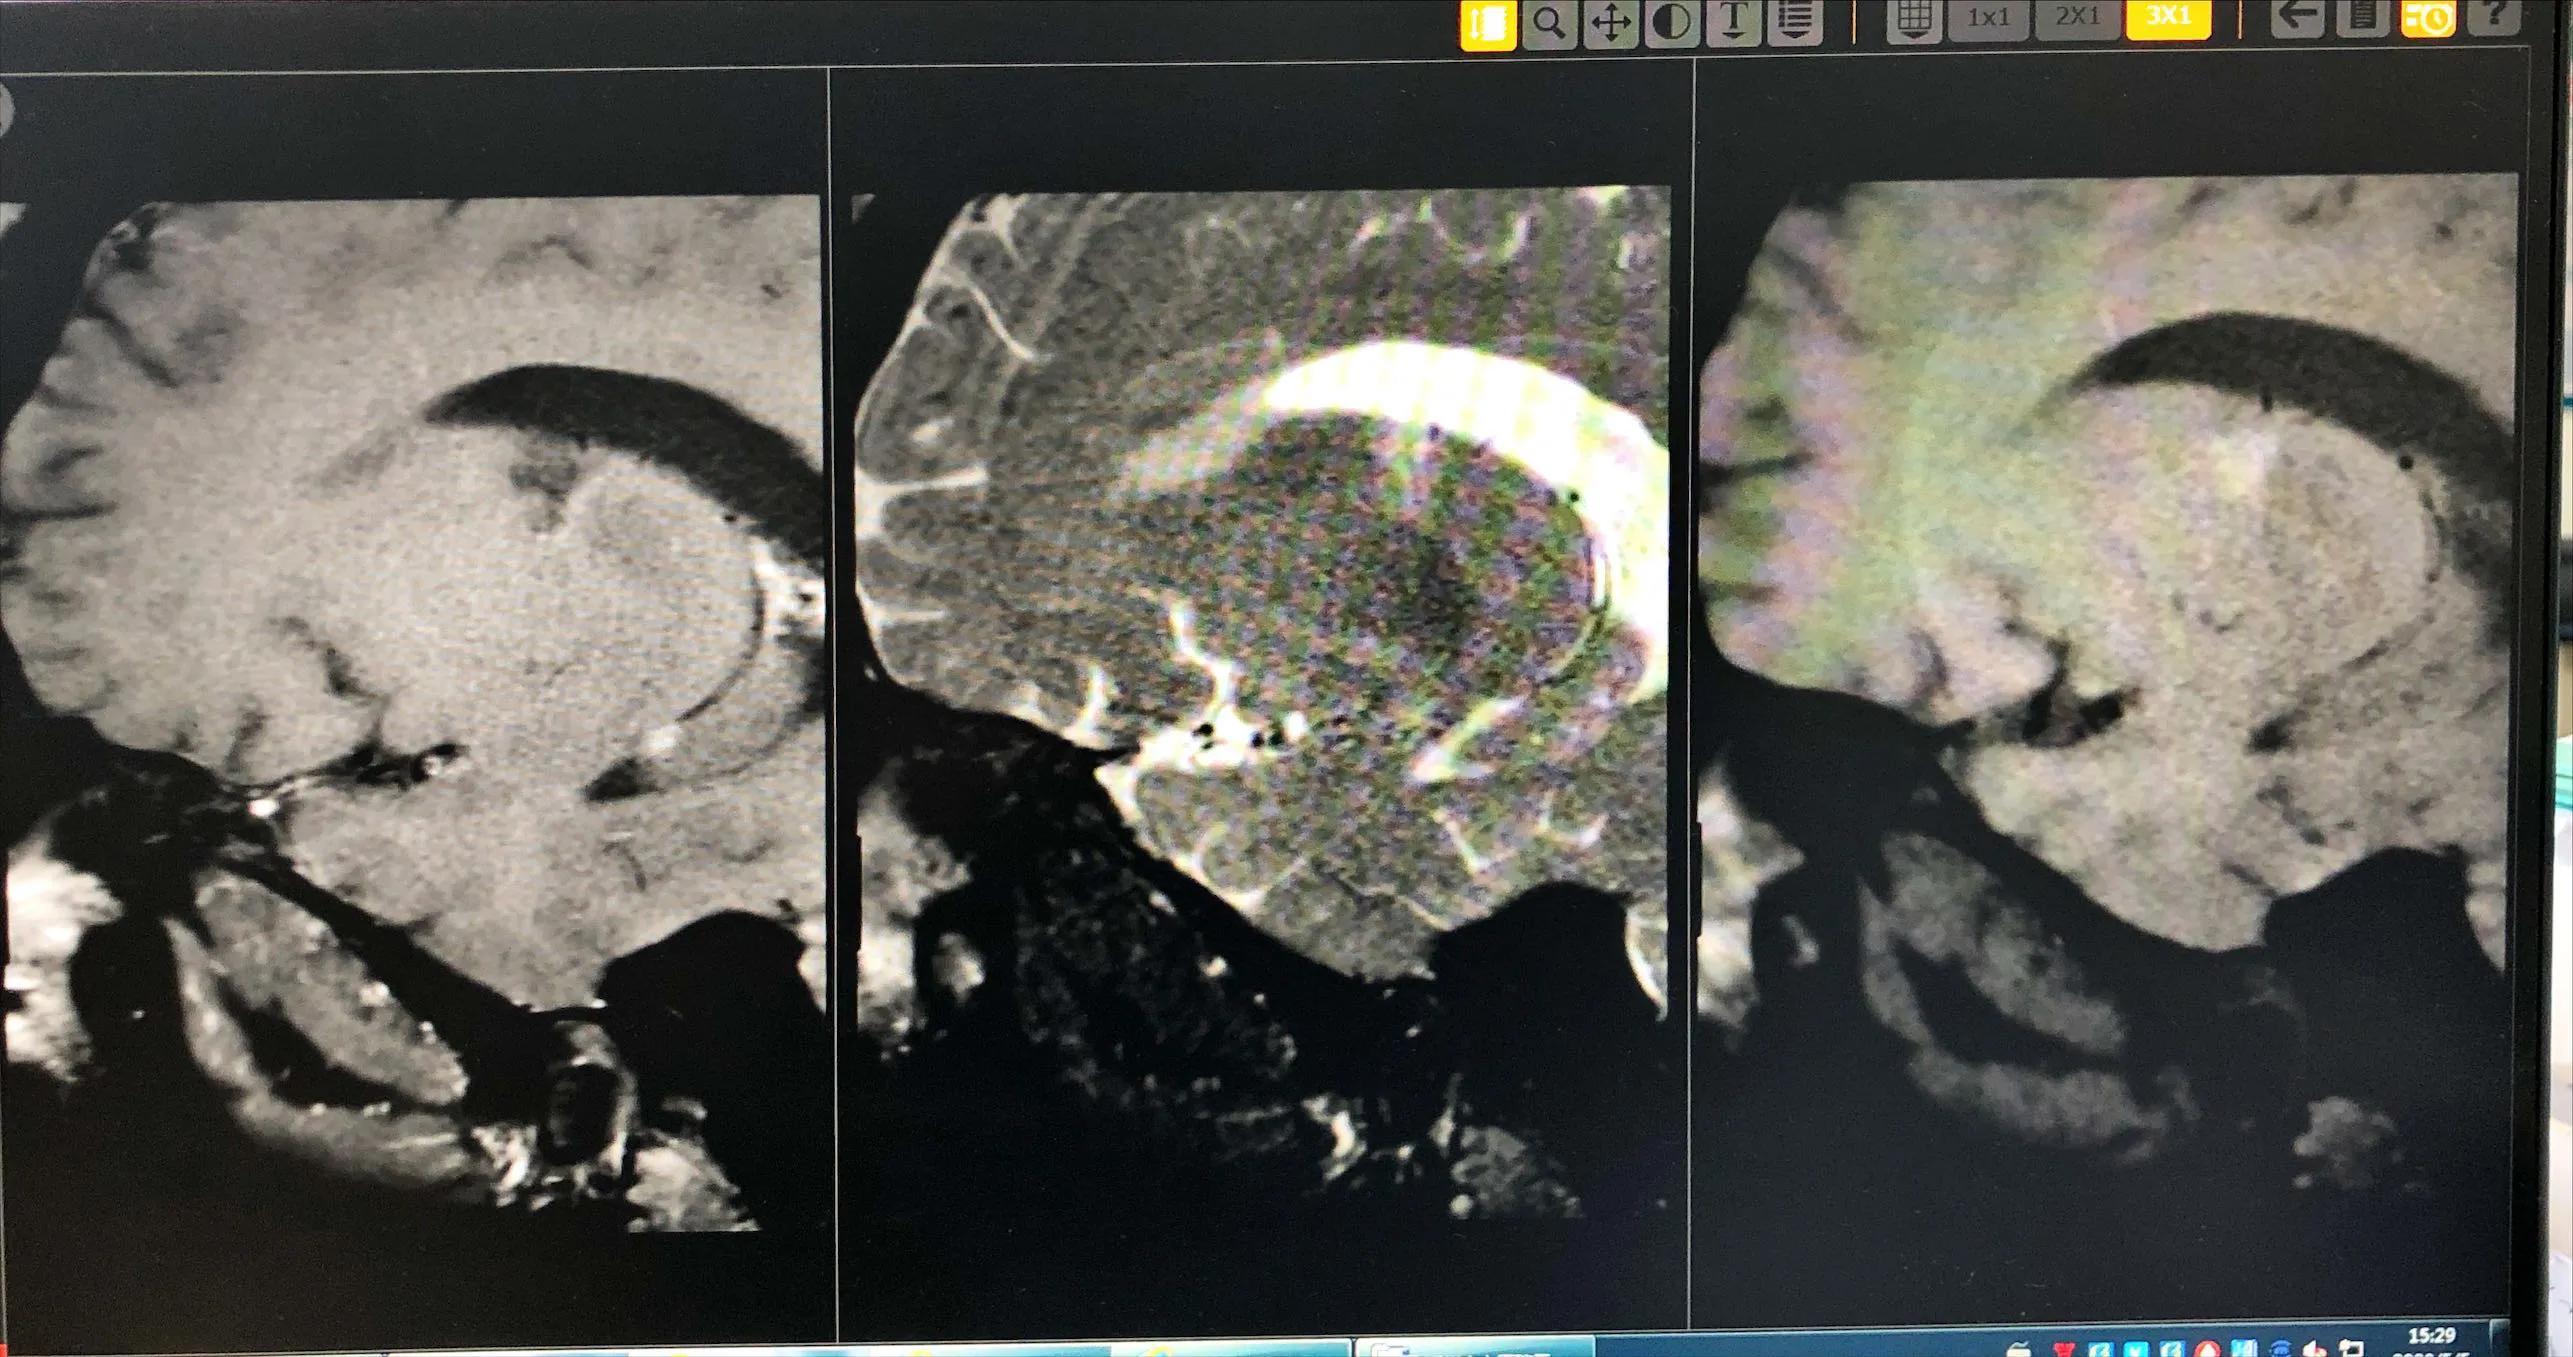

病例1.男,32岁,以“右上下肢麻木无力9天,加重1天”为主诉入院。既往史:既往体健,否认“冠心病、高血压、糖尿病”病史,抽烟2包/天·15年,酗酒:半斤/4~5次·周;9天前患者无明显诱因出现右上下肢麻木无力,右侧肢体症状持续呈波动性,严重时有右上下肢仅能在床上平移,无头痛呕吐、意识障碍、视物不清、肢体抽搐、大小便*禁失**等,遂于郑州人民医院就诊,磁共振回示:2022年06-19郑州人民医院:1.左侧枕叶、额顶叶新近脑梗死;2.脑桥偏左侧、双侧基底节区、侧脑室旁、辐射冠、半卵圆中心区、额顶叶皮层下缺血灶;3.左侧基底节区、侧脑室旁软化灶伴胶质增生;4.右侧大脑前动脉A1段轻度狭窄;5.左侧大脑中动脉M1-3段、右侧M2段轻度狭窄;6.双侧大脑后动脉P2段轻度狭窄;7.左侧椎动脉优势,诊断为“急性脑梗死”,给予对症支持治疗(具体不详)后症状稍好转。1天前,患者感右上下麻木无力较前明显加重,右侧肢体完全不能抬起,就诊我院,以“脑梗塞”收住。查体:BP150/110mm Hg,神清、中枢性面舌肢瘫、右上下肢肌力Ⅳ级,粗测右侧面及肢体浅感觉减退,右侧巴氏征(±)NIHSS评分4分。斑块分析提示:高分辨磁共振成像示左侧大脑中动脉M2段重度狭窄伴动脉粥样硬化斑块形成(考虑不稳定斑块)。

图片来源于病历